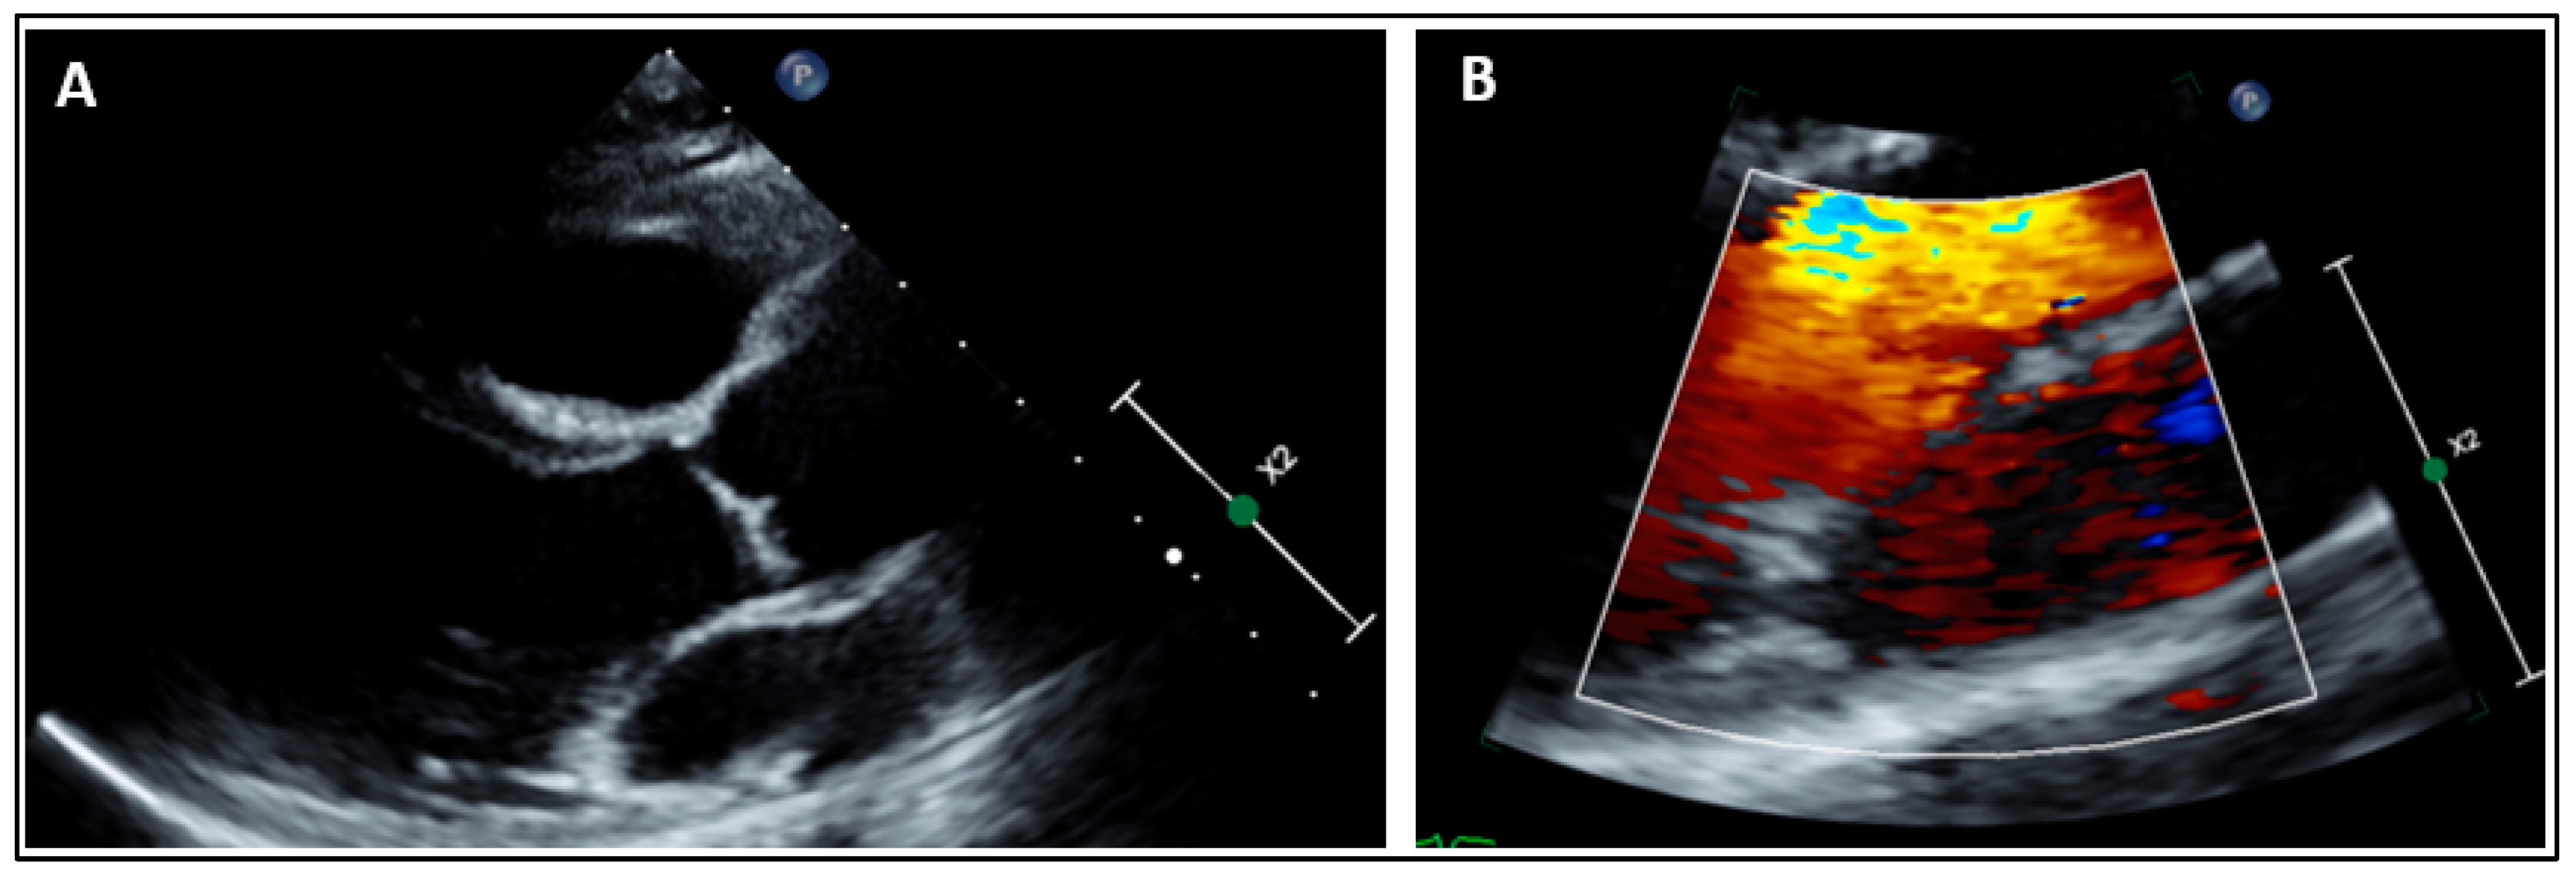

More recently, another daughter of the family has been recruited for clinical and genetic screening. Her cardiac evaluation showed no MVP (Figure 4). Sanger sequencing revealed the absence of the SCN5A:p.(Ala572Asp) variant. She carried only the common SCN5A:p.(His558Arg) polymorphism (Figure 5).

Figure 4.

Parasternal long axis view ruling out any mitral valve prolapse (A). Mitral valve leaflets are thin without chordae elongation. Parasternal long axis view with color Doppler ruling out any mitral regurgitation in systole (B).